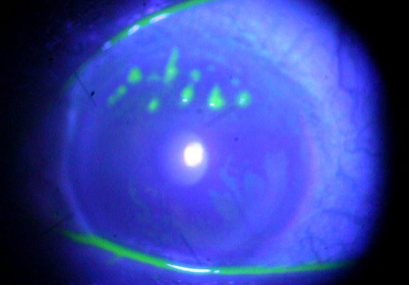

也就是说,角膜上并非真的长出“树枝”,而是由于病毒感染,加上它的形态恰好与树枝相似,才被称为树枝状角膜炎。

(用特殊的荧光染色方法后呈现的树枝状角膜炎)

这种角膜炎发病急,患者会伴有畏光、流泪、眼疼、异物感等症状。如果患者不及时进行适当治疗,树枝状角膜炎就会进一步发展,成为地球状角膜溃疡或圆盘状角膜炎。